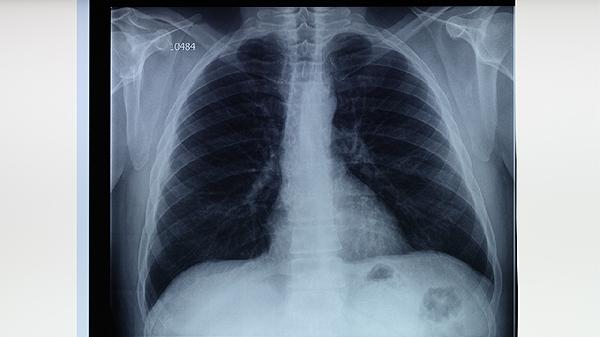

胸部X线可显示肺结核典型病变,如上肺野浸润影、空洞形成或纤维钙化灶。早期表现为斑片状阴影,进展期可出现干酪样坏死伴透亮区。该检查对粟粒型肺结核诊断敏感性较低,需联合CT检查。检查时需去除金属物品,孕妇应告知医生并评估必要性,必要时采用铅防护措施。